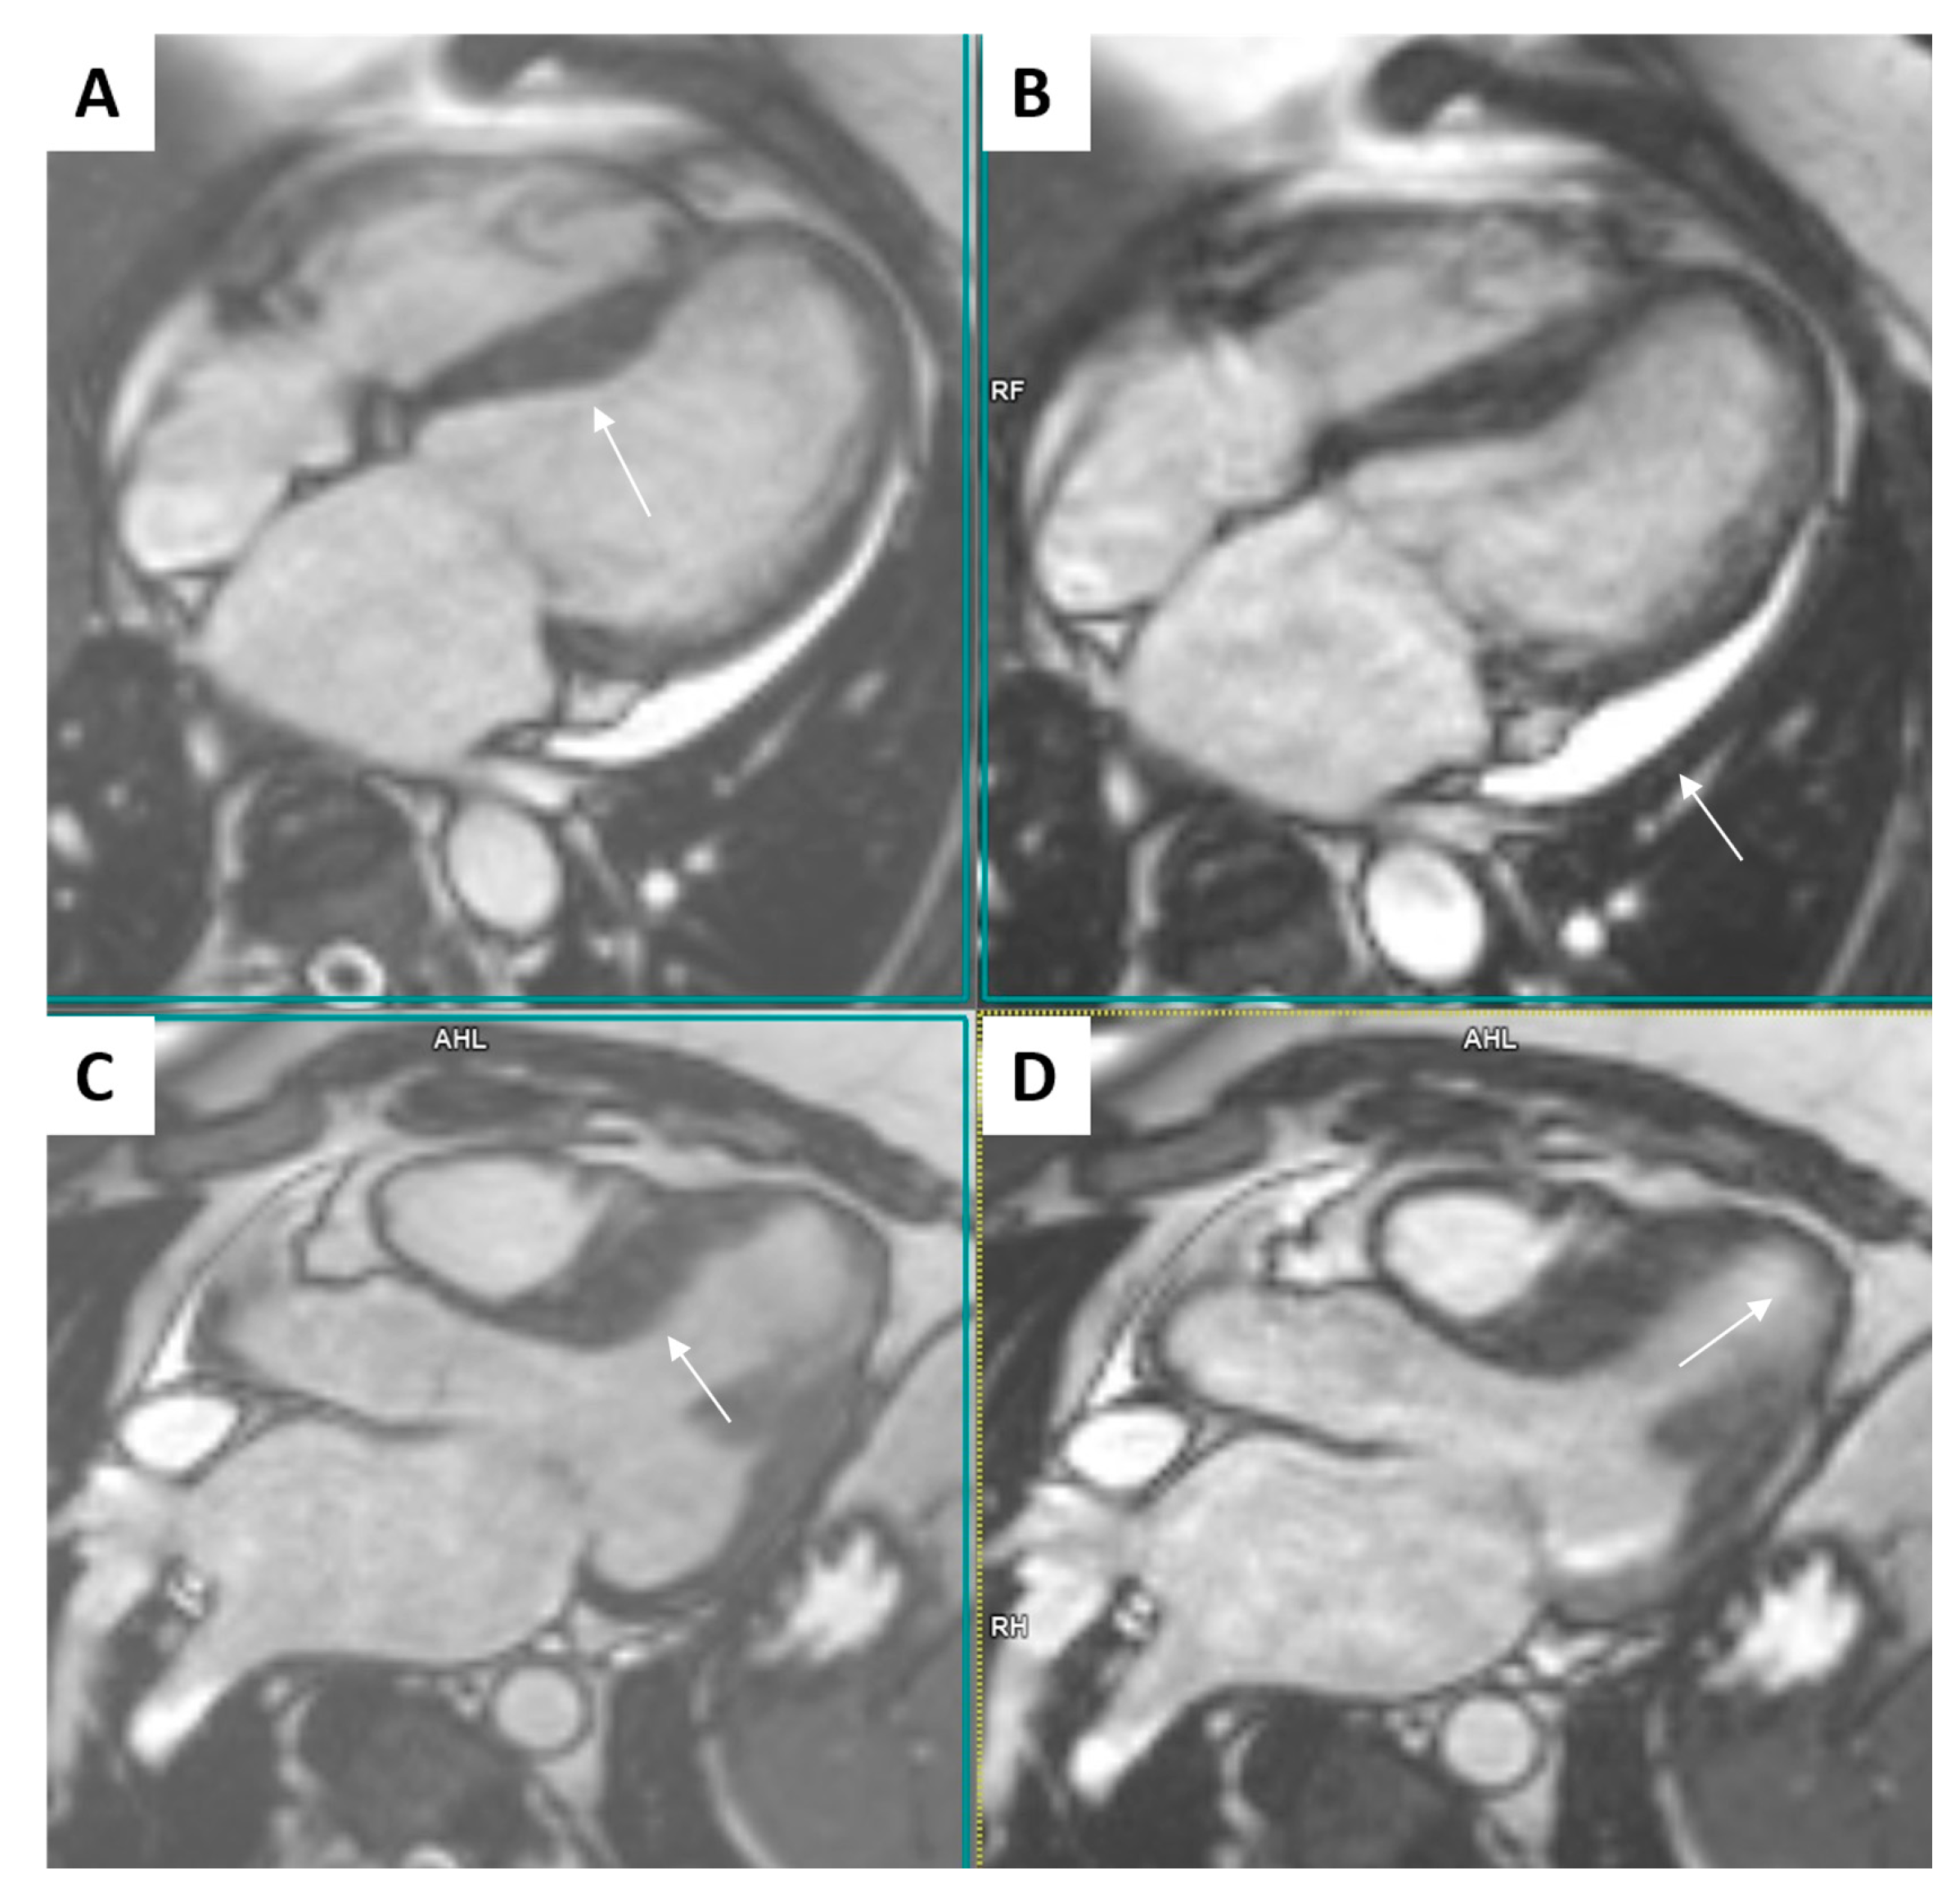

2.2. Cardiac Magnetic Resonance (CMR)

| March 2021, age 45 | First episode of decompensated heart failure, NYHA III-IV class; A new episode of persistent AF, duration longer than two months | Management of failure according to guidelines; TEE not performed due to INR not being in target; Asymmetric left ventricular hypertrophy and reduced ejection fraction noted; Further diagnostic work-up recommended—cardiac magnetic resonance (CMR) and genetic testing; Test for Anderson–Fabry disease—negative; CMR study positive for cardiomyopathy with diffuse fibrosis, possibly hypertrophic or infiltrative.  | At admission: Amiodarone 400 mg; Torasemide 20 mg; Irbesartan 75 mg; Acenocoumarol; At discharge: Torasemide 50 mg; Spironolactone 50 mg; Acenocoumarol; Bisoprolol 5 mg; Sacubitril/valsartan 2 × 24/26 mg; Allopurinol 150 mg; Dapagliflozin 10 mg  |